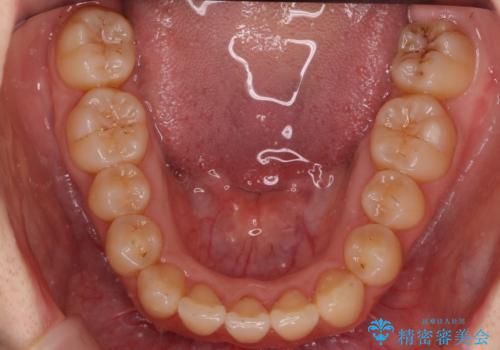

- 歯のがたつきを主訴に来院。

左右とも奥歯のがたつきがあり、左奥はすれ違っていました。

また、右奥は反対咬合になっていました。

下の前歯を一本抜歯しています。(抜歯の本数は最小限にしています。)